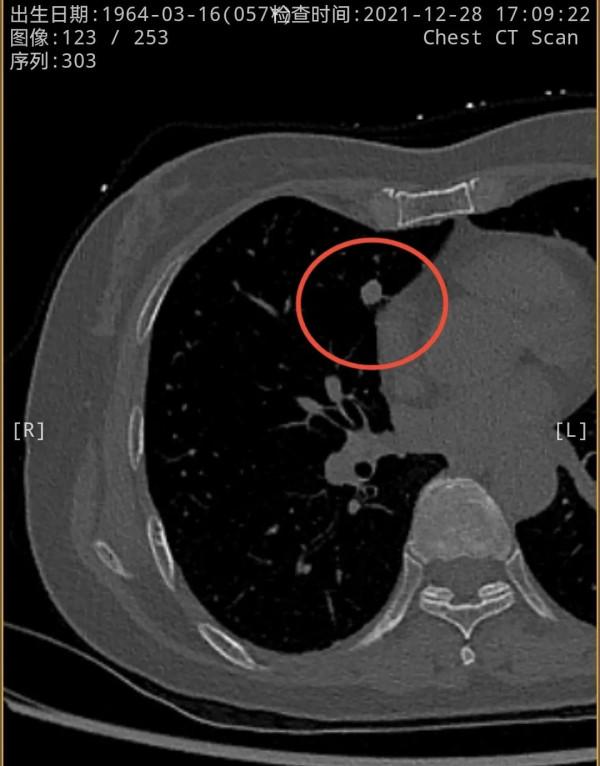

我們先來看2021年12月的,右肺多發實性結節,邊緣相對平直,膨脹性不明顯,紅色圈起來的主病灶周邊一圈密度高,中間密度低,還有點狀高密度,考慮肉芽腫性炎伴壞死(區域性纖維鈣化),次病灶藍色圈起來的形態也是類似的,骨窗看也是中間密度低,而周邊一圈密度高。那麼再來看2019年時是如何的呢?假如是惡性,應該有進展。但我們閱片後發現並沒有大的變化,由於掃描條件不同,中間密度低在平掃上不明顯,紫紅圈起來的和綠色圈起來的分別對應主病灶和次病灶。但當時有區域性靶掃描,結果形態與2年後的沒什麼區別,當時也已經是周邊一圈密度高,而中間密度低且均勻。所以此兩灶可基本認定為肉芽腫性炎伴壞死,可安全隨訪。最好半年查一次(因為正常沒結節也一年查一次呢)。